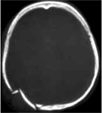

Ascesso

cerebrale |